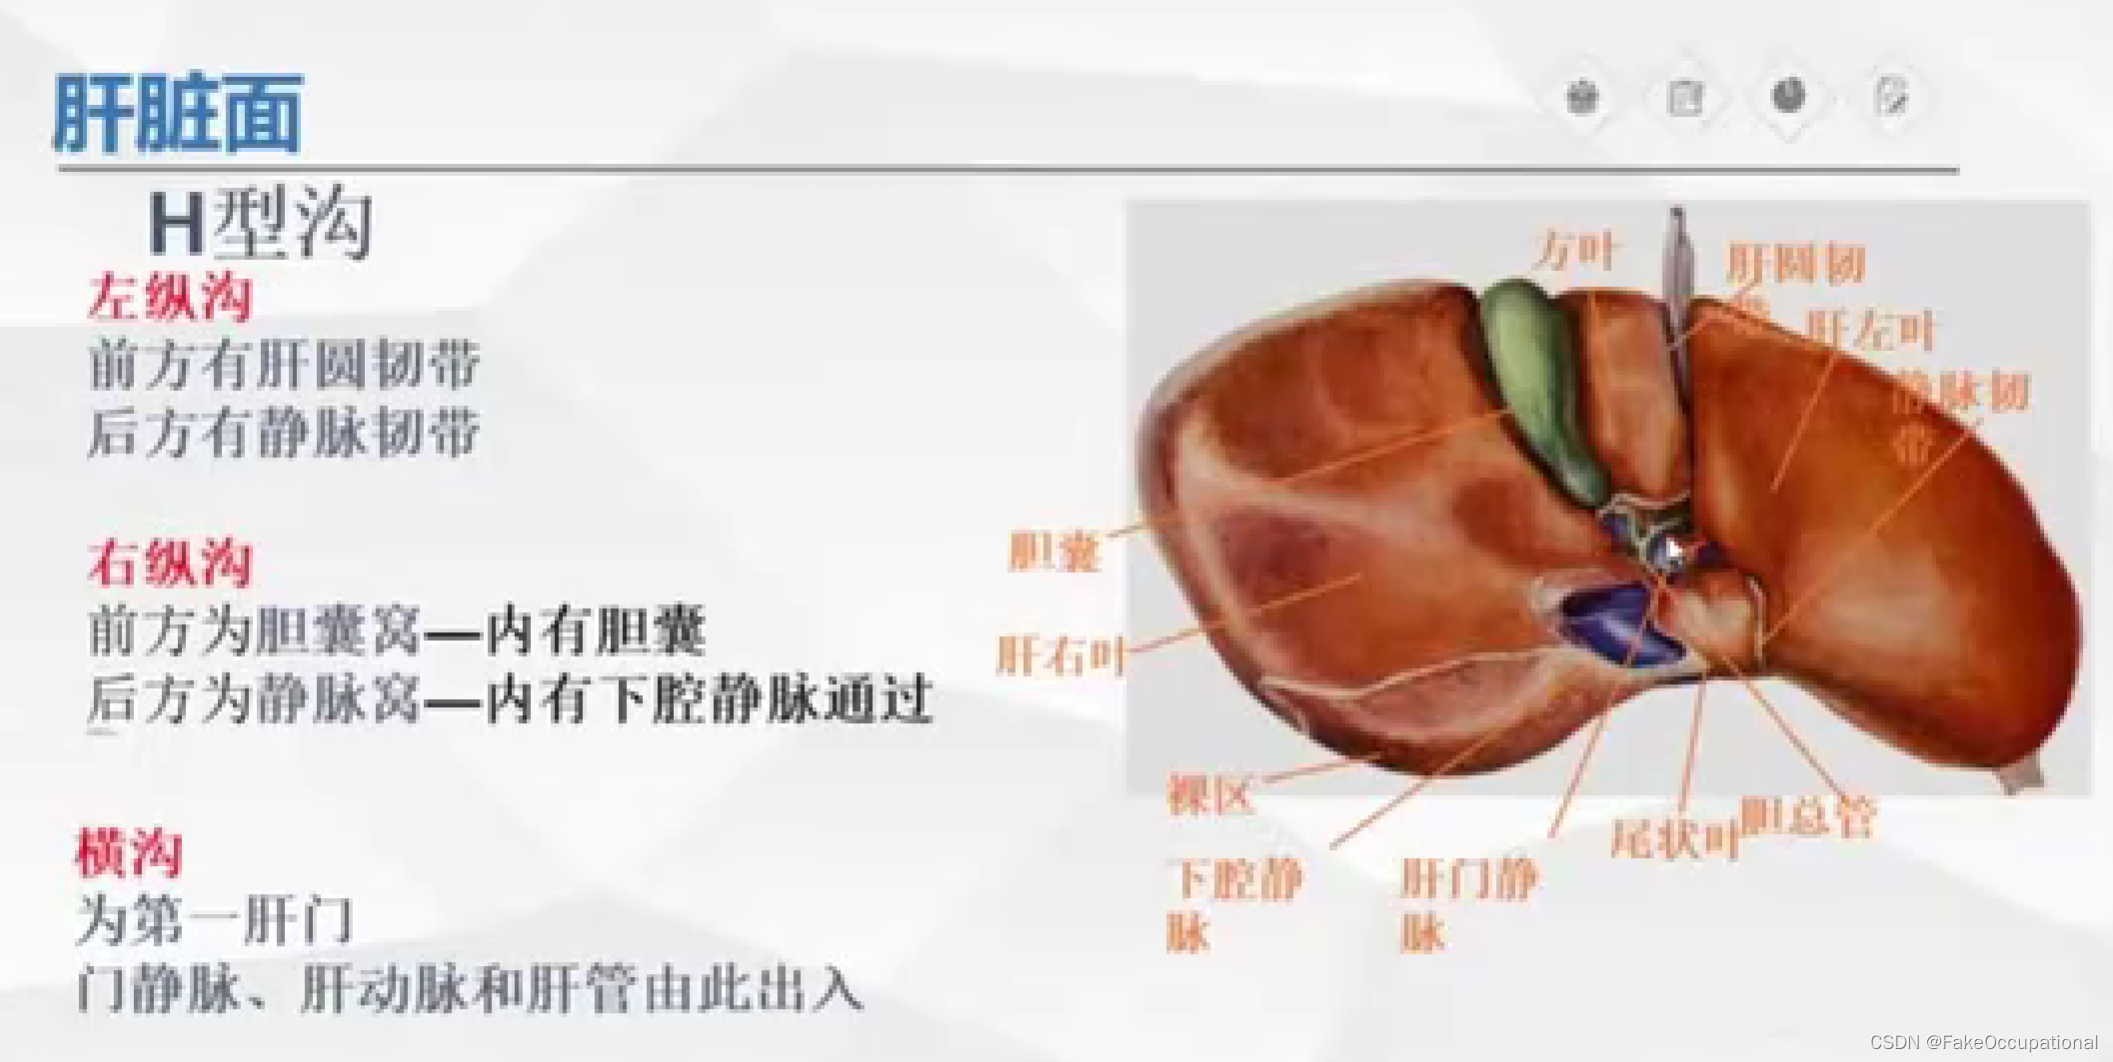

肝脏解剖概要